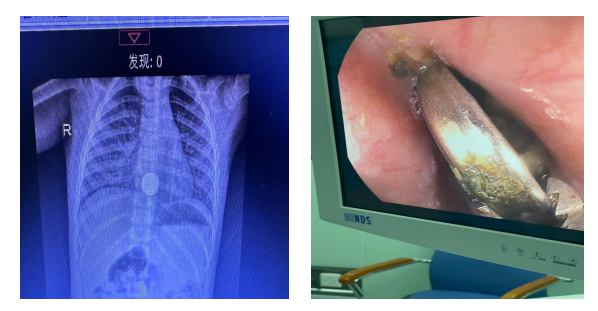

近日,济宁市第一人民医院儿科东院消化病区成功为一名2岁幼儿实施气管插管全身麻醉下食管异物(纽扣电池)急诊取出术,患儿术后顺利康复出院。

纽扣电池在食管内嵌顿2-2.5小时,就可能引发食管严重烧伤、瘢痕狭窄等并发症,危及生命,必须争分夺秒取出。该患儿误吞电池前1小时曾间断进食,胸腹部CT显示胃内容物较多,胃镜下异物取出极易发生误吸、呛咳,手术风险极高。

手术在手术室气管插管全身麻醉下进行,麻醉科团队全程严密监护,吕红艳副主任医师凭借精湛的内镜技术,联合无痛内镜部程丽君主管护师精准操作,顺利将纽扣电池完整取出,患儿转危为安。术中可见食管黏膜腐蚀损伤明显,存在潜在穿孔风险,经5天严密住院观察与对症治疗后,患儿康复出院。